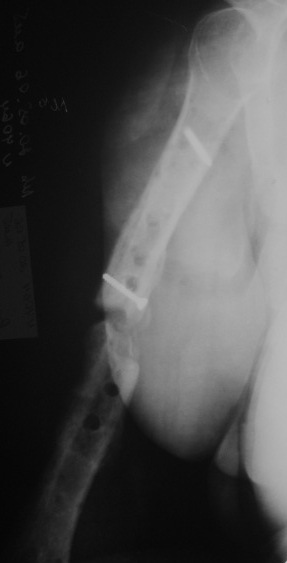

Несросшийся перелом диафиза

Уважаемые коллеги, пациентка лечится с переломом диафиза плеча 1.5 года.

Первоначально синтез пластиной,через 1 год перелом фиксаторов, АВФ на 4 месяца, 2 месяца в гипсовой лонгете и повторная травма. Планируется синтез интрамедуллярным гвоздем. Стоит ли максимально плотно подгонять концы отломков, удалять избыточную костную мозоль или достаточно жесткого синтеза с плотной посадкой гвоздя с ликвидацией ренгенологического диастаза?